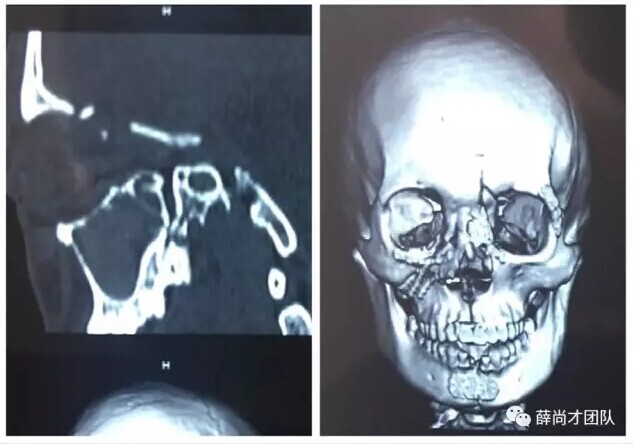

甘肃省二院眼科开展经眼眶视神经减压术使许多外伤失明的患者重见光明------2017-04-28 发布时间:2017-04-28 来源: 作者:

本文转自:薛尚才团队